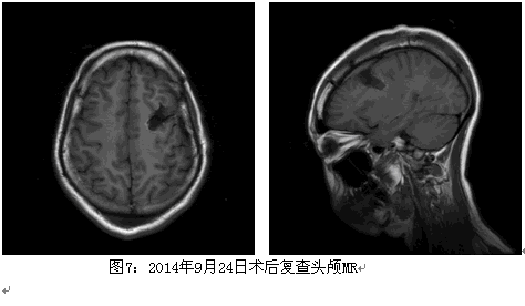

患者考虑为药物难治性癫痫,且曾有发作致脑外伤的事件,纳入术前评估。结合相关检查结果,脑电图报告:异常脑电图III(清醒/睡眠),间歇期:弥漫性,左额-中央著,发作期:临床:右侧偏转。EEG:发作型,左半球。头颅MRI薄层扫描:1.右侧颞叶皮层(含颞极)、邻近右侧额下回多发软化灶并胶质增生、含铁血黄素沉着;右侧额叶眶回局部慢性小出血灶并含铁血黄素沉着可能性大;2.待排左侧额上回与额下回交界处局灶性脑皮质发育不良;3.考虑左侧乳突炎症改变。视野检查无异常。韦氏测试:智商84,言语76,操作96,记忆<51。癫痫定位考虑为额叶外侧面,定侧为左侧,病因考虑皮层发育不良;经全中心讨论后计划一次性切除手术,切除范围,后界:中央前沟后壁,上界:额上沟外侧壁,下界:额下沟外侧壁1cm;前界:额中回后部。予术中唤醒下切除,切除过程中嘱患者讲话并交流,病变质地稍硬,将病变全部切除,约3.5*3.0*3.0cm,术后患者无语言功能障碍,随访近3个月无发作,术后病理回报:局灶性皮层发育不良FCD Ib型。

该患者病变主要位于额中回,为额眼区之一,该患者发作时头眼右侧偏转可能与额眼区的眼球平稳追踪运动相关,而该患者发作时的视觉先兆推测与视觉通路中的某一脑区相关。

局灶性皮层发育不良(FCD)是皮质发育的一种异质性疾病,目前多认为由于神经母细胞部分完成移位后受到遗传或环境因素影响而发生。脑发育不良区域一直被认为是引起癫痫的责任病灶,多数通过切除术后癫痫控制良好,但远期疗效还需要进一步随访。随着研究的不断深入,临床手术治疗效果有望得到进一步提高。